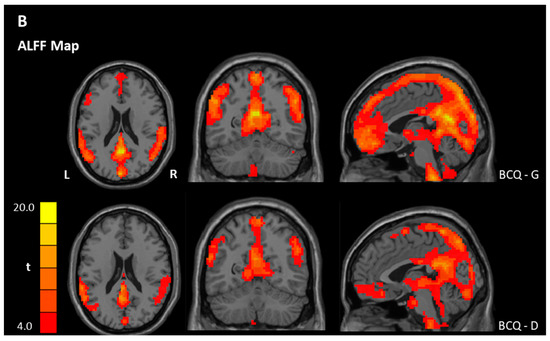

3.3. ReHo and ALFF Analyses

| ALFF | |||||||

| Within-group ** | |||||||

| BCQ-Gentleness | |||||||

| Gentleness > 0 | PCC | 23 | 11639 | 17.34 | −3 | −54 | 21 |

| Gentleness < 0 | NS | ||||||

| BCQ-Deficiency | |||||||

| Deficiency > 0 | OFC, Left | 11 | 161 | 6.79 | −33 | 33 | −18 |

| Deficiency < 0 | Precentral gyrus, Left | 6 | 29,955 | 52.63 | −18 | −18 | 54 |

| Between-group * | |||||||

| Gentleness > Deficiency | NS | ||||||

| Gentleness < Deficiency | Pons/Cerebellum, Left | 85 | −3.86 | −12 | −36 | −54 | |